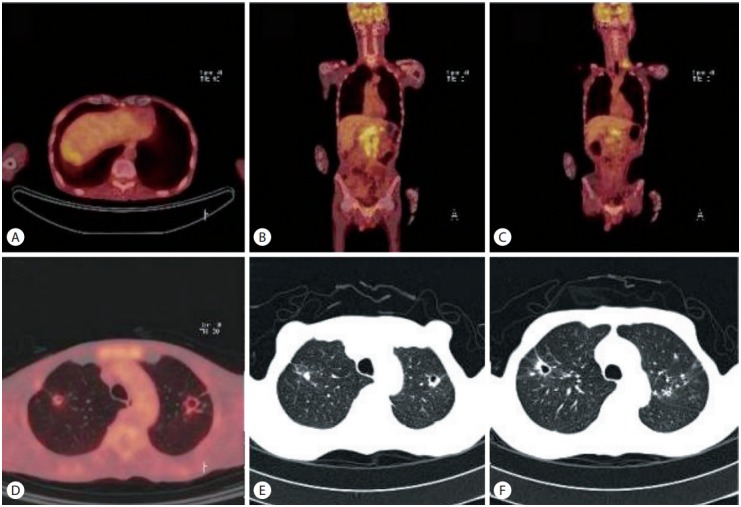

A 58-year-old man was admitted to our hospital for investigation of a liver mass with extensive LN enlargement that had been detected during the evaluation of general weakness and weight loss. Although he had been found to be positive for hepatitis B virus antigen during a routine medical check in his 30s, he did not visit the physician or hospital for follow up. Physical examination showed no abnormal findings. Laboratory data at admission to the hospital showed anemia [hemoglobin (Hb) 11.0 g/dL], thrombocytopenia (platelet count 52×103/μL) and mild elevated liver enzymes. Further test showed normal prothrombin time percentage, high levels of tumor markers [α-fetoprotein: 15.62 ng/mL (normal range ≤10 ng/mL) and des-γ-carboxyprothrombin: 295 mAU/mL (normal range 0–40 mAU/mL)]. Abdominal computed tomography (CT) showed several masses with or without central necrosis at the liver segements 6, 7, and 8 (diameter of the largest one: 5 cm). The masses shows early enhancement (Fig. 1A, B) and delayed wash out (Fig. 1C, D). Adding to this, CT demonstrated multiple enlarged LNs along the celiac axis, common hepatic artery, portocaval, paraaortic, aortocaval, and retrocaval area (Fig. 1E). In addition, magnetic resonance imaging also showed multiple HCCs with multiple enlarged LNs (Fig. 1F-J). Positron emission tomography (PET)-CT and chest CT were performed to evaluation of extrahepatic metastasis. PET-CT showed increased fluodeoxyglucose (FDG) uptake in the liver and multiple metatatic LNs including left supraclavicular LN and cavitary pulmonary nodules in both upper lobe (Fig. 2A-D). Chest CT showed multiple thick-walled cavitary lesion, branching linear opacities and clustered centrilobular nodules at both upper lobe (Fig. 2E, F). Based on these findings, we could suspected HCCs with systemic LNs and lung metastasis. However the treatment was suspended due to worsening of the general status. During the supportive care, follow up blood tests showed more worsen anemia (Hb 6.9 g/dL) and thrombocytopenia (platelet count, 17×103/uL). The suspected diagnosis was HCC with bone marrow metastasis or other hematologic disease, taking into consideration the absence of other causes such as marked splenomegaly, liver function test deterioration, bleeding or infection. Accordingly, a bone marrow biopsy was performed and showed only a few normal hematopoietic cells and abundant tumor cells (Fig. 3). Based upon the diagnosis of HCC metastasis to the bone marrow, LNs, and lung metastasis, we started therapy with sorafenib. However, treatment was discontinued due to worsening of general weakness and grade 2 diarrhea. Since then, because the patient and patients family wanted to stop the treatment and to perform only supportive care, we did general care and the patients liver function deteriorated rapidly and died 2.3 months after the detection of the liver mass.

Figure 2.

Positron emission tomography (PET)-CT and chest CT. (A) PET-CT shows mildly increased fluodeoxyglucose uptake in the liver dome (SUVmax : 3.6). (B, C) Multiple FDG uptake is noted in retroperitoneal, gastrohepatic, and left supraclavicular lymph nodes. (D) Cavitary pulmonary nodules is also noted in both upper lobe. (E, F) Chest-CT shows multiple thick-walled cavitary lesion, branching linear opacities and clustered centrilobular nodules at both upper lobe.